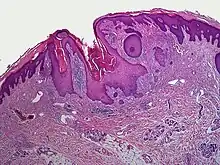

A dilated pore, also known as a dilated pore of Winer, is a cutaneous condition characterized by a solitary, prominent, open comedo on the face or upper trunk of an individual.[1]:675 Louis H. Winer is credited with discovering the dilated pore. [2][3]